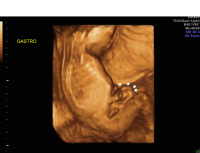

Gastroschisis, which is a type of “ventral wall defect,” is diagnosed when some of the contents of the abdomen protrude out of the body through an opening in the abdominal muscles near the umbilical cord. Having no protective covering, the organs are exposed to amniotic fluid and can become swollen or damaged. Gastroschisis occurs in approximately one in 5,000 births and is typically an isolated birth defect.

Gastroschisis free bowel

After birth, the organs will be protected by a sterile sheet known as a “silo.” Gradually, the organs will be placed back into the abdomen, at which time the abdomen will be closed surgically. Overall, most children with gastroschisis are able to live very full, active, and productive lives with no long-term health problems.